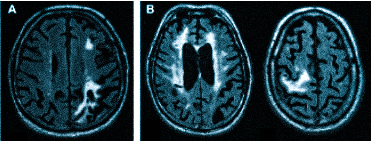

Если делать МРТ, когда не болит голова

Множественные ишемические очаги при сосудистой деменции на МРТ: отсутствие памяти на недавние события и неадекватное поведение не являются нормой для пожилых людей. Своевременная диагностика деменции и патогенетическая терапия могут замедлить прогрессирование болезни.

- демиелинизацию при рассеянном склерозе и других атрофических процессах;

Что покажет МРТ при мигрени? Приступ мигрени сопровождается расширением сосудов мозга, за которым следует резкий спазм. МР-томограф фиксирует нарушения кровотока во время приступов и выявляет ишемические очаги, которые могут появляться в большом количестве.

При диагностике может быть назначено МРТ головного мозга для проверки сосудистых патологий. Мигрень возникает из-за временного сужения сосудов в мозге, что приводит к спазму. МРТ позволяет выявить нарушения кровотока и ишемические изменения.